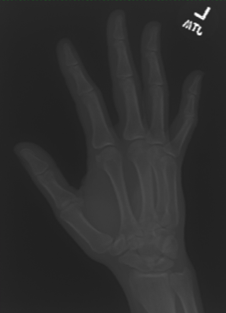

In this work, we focus on a subset of the MURA dataset [17] containing only hand images. In total, we have 5,543 images of 2,018 studies of 1,945 patients. Each study is labeled as negative or positive, where positive means that there was an anomaly diagnosed in this study. There are 521 positive studies, with a total of 1,484 images. Figure 1 shows some examples from the dataset. In summary, our contributions are as follows:

The first step in our pipeline is to detect the X-ray image carrier in the image. To this end, we apply OpenCV’s contour detection using Otsu binarization [14], and retrieve the minimum size bounding box, which does not need to be axis-aligned. This works sufficiently well as long as the majority of the image carrier is within the image (cf. Figure 3). However, the approach might fail for heavily tilted images or those where larger parts of the image carrier reach beyond the image border.

Hand Localization

To further improve the detection of hands, and in particular split the images where two hands are depicted on one image, we manually labeled approximately 150 bounding boxes in the images. Using this small dataset, we fine-tune a pre-trained single shot multibox detector (SSD) [12] with MobileNet as taken from TensorFlow. An exemplary results can be seen in Figure 3.

Foreground Segmentation